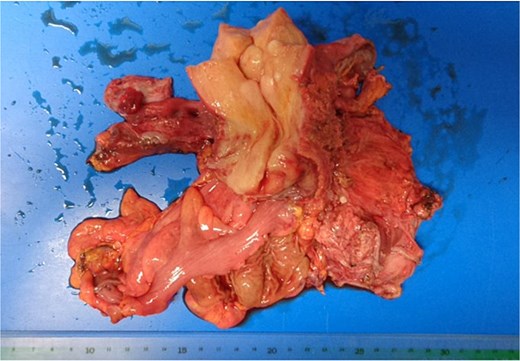

At the risk of traumatic injury, a stent was placed in the right ureter before surgery. Laparotomy revealed endometrial cysts in the bilateral ovaries. The peritoneum was found to be free from dissemination of the cancer, and the tumor had grown beneath the peritoneum to infiltrate the rectovaginal septum, the uterus, the vagina, the rectum, the parametrium including the bilateral cardinal ligaments, the ureters, and the bladder. Tumor invasion was more extensive on the left side. Carcinoma appeared to infiltrate into the bladder as well as the lower segment of the right ureter, but separation of the bladder and the ureter from carcinoma tissue was barely feasible. Hysterectomy, partial vaginectomy, bilateral salpingo-oophorectomy, partial rectal resection and left ureterectomy, omentectomy, and colostomy were performed (Fig. 4). However, the surgical resection was incomplete, and considerable amounts of cancer tissue were retained, especially in the left pelvic wall.

Surgical specimen. The rectum and left ureter were resected together with the uterus.